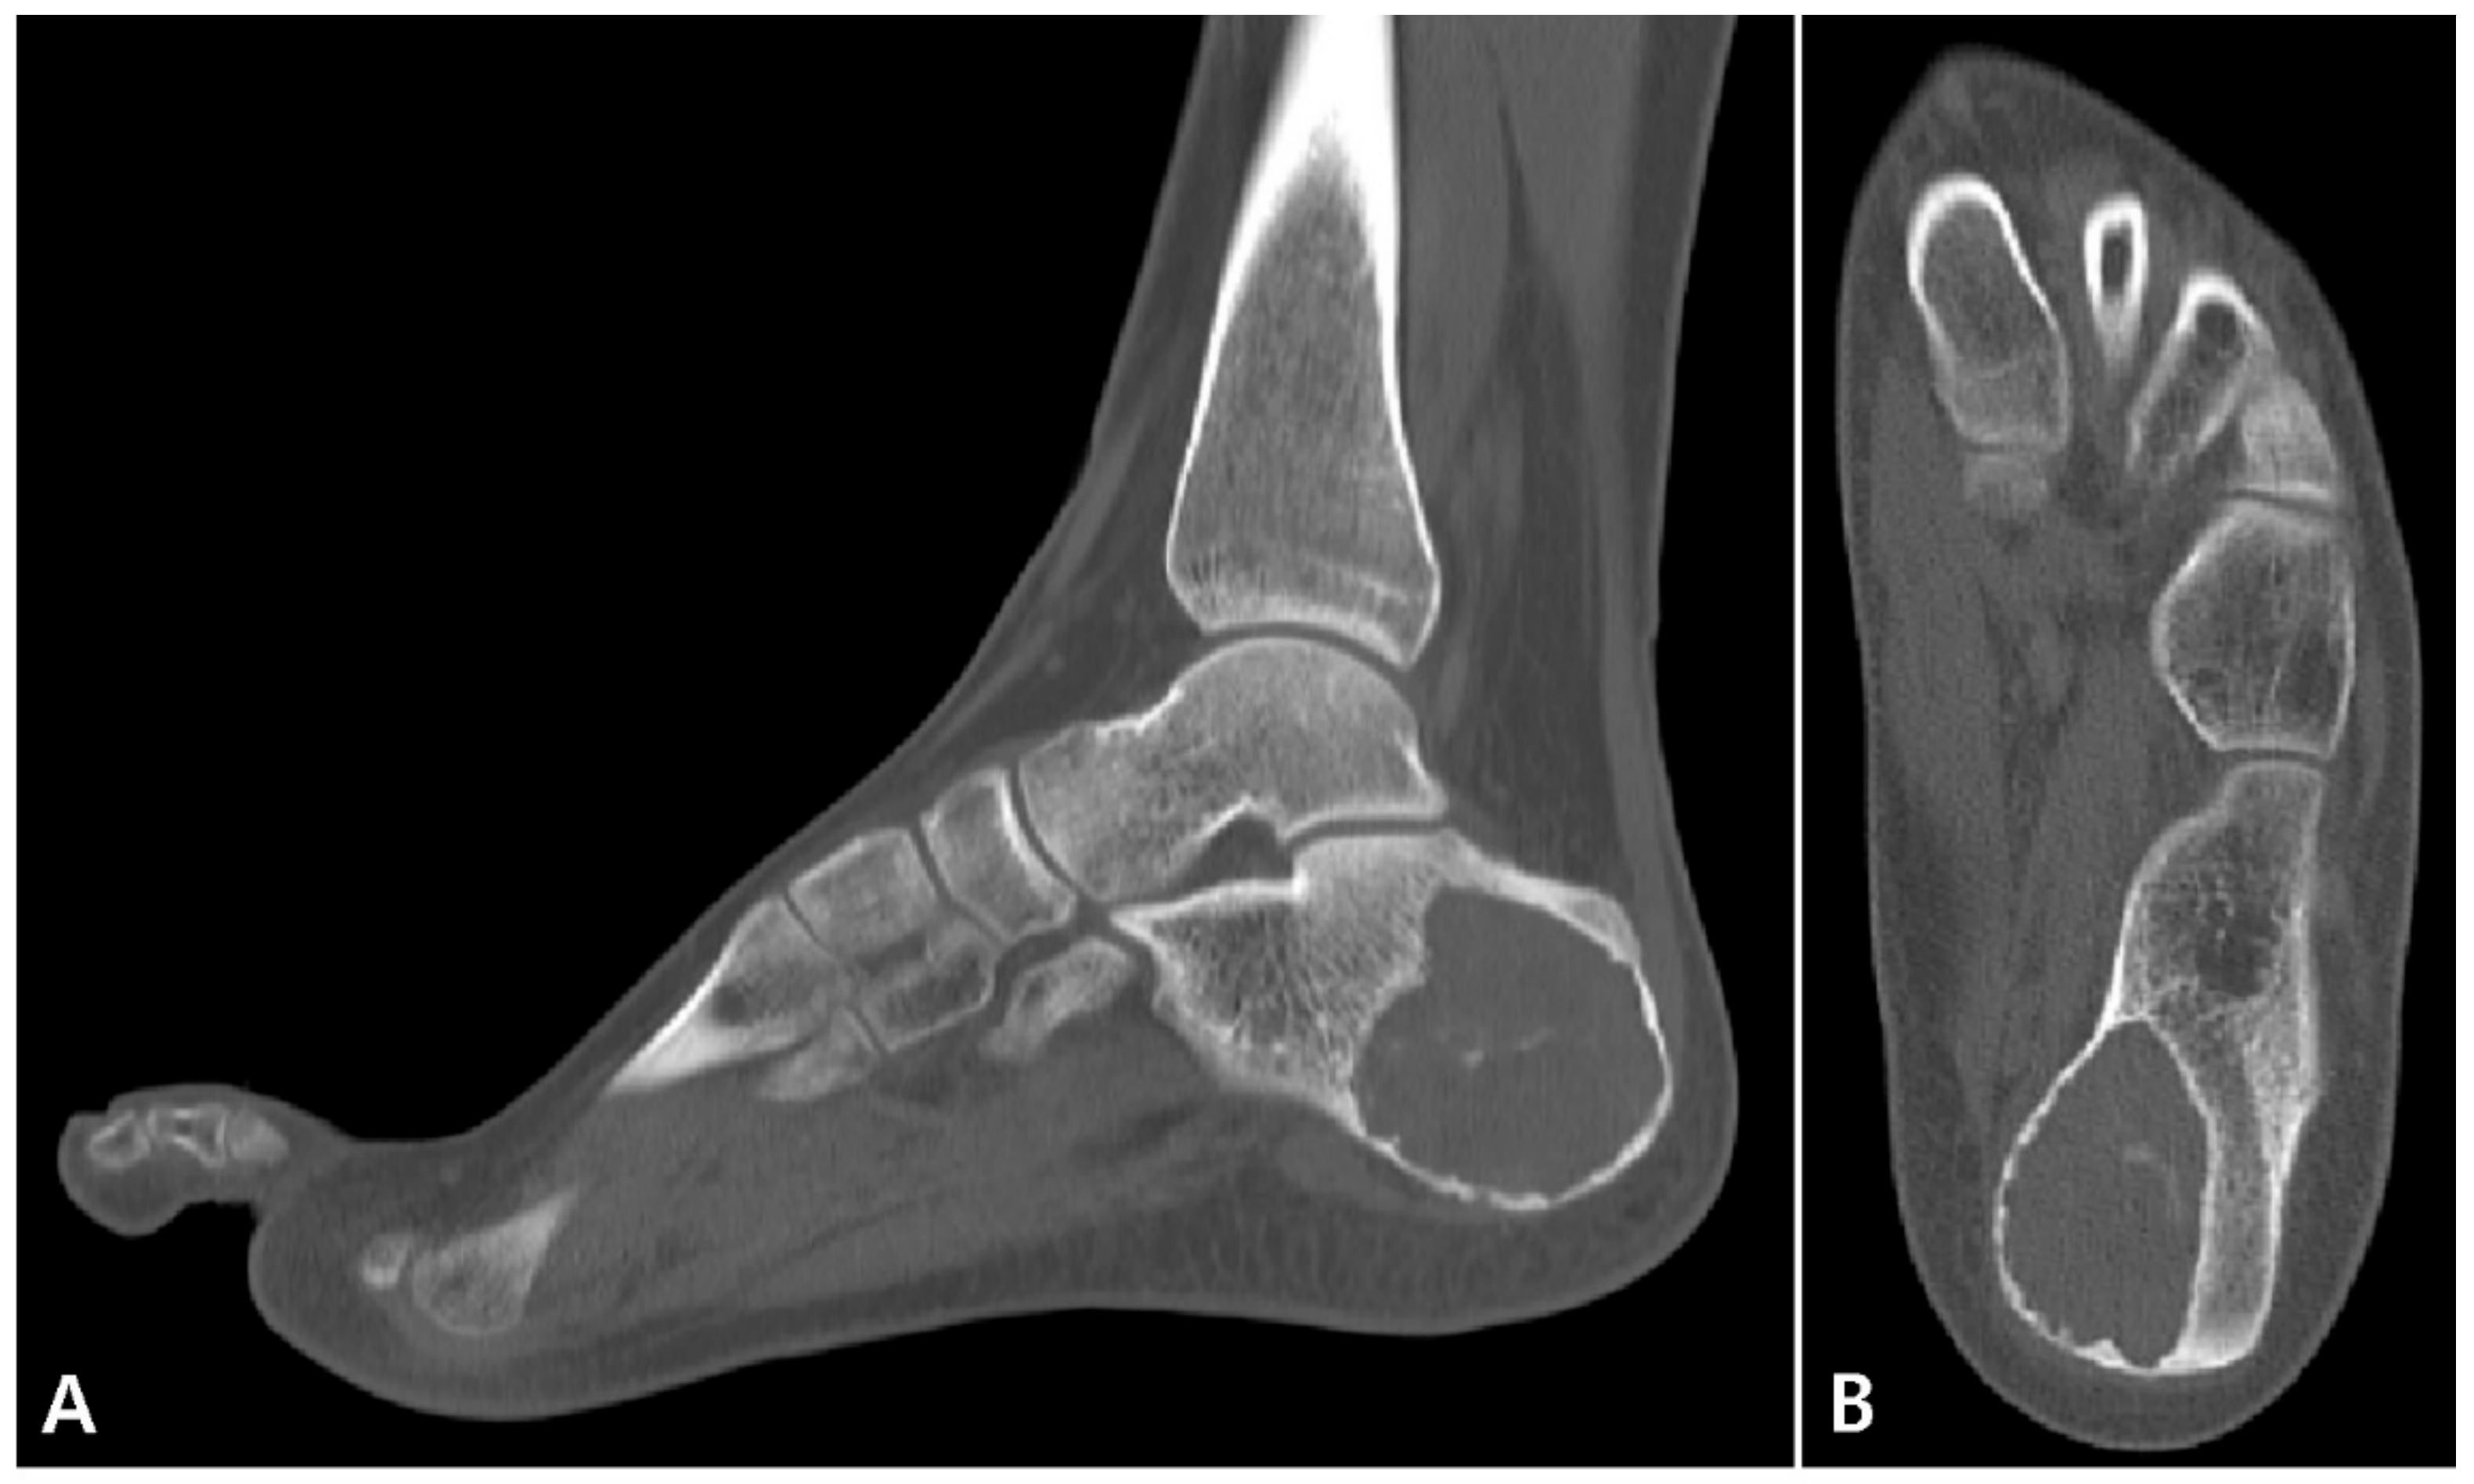

2. Case Presentation

2.1. Preoperative Evaluation

2.2. Surgical Procedure